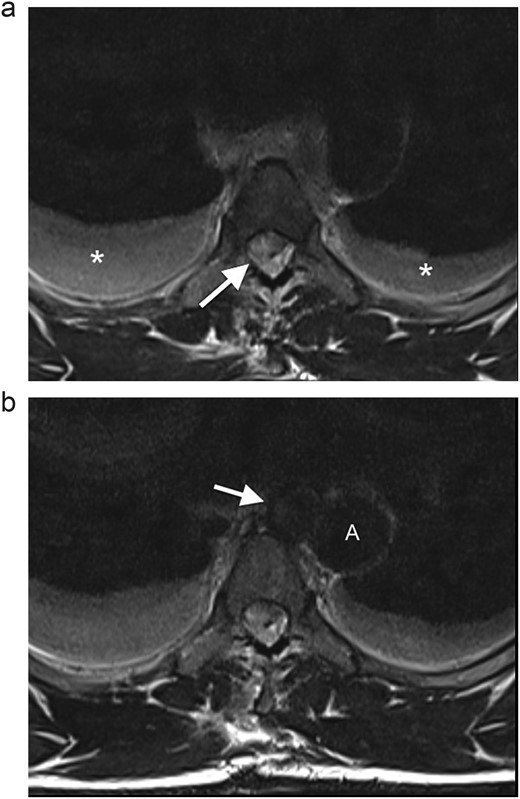

(a) Axial T2WI MR at the midthoracic level demonstrates an epidural hematoma in the right lateral spinal canal with compression of the cord (arrow) and bilateral hydrothoraces (*). (b) Axial T2WI MR shows a round lesion (arrow) inseparable from the medial aspect of the mid-thoracic aorta (A), with an isointense signal to the thoracic aorta.

The MRI also revealed a well-circumscribed lesion in the posterior mediastinum at the T4–5 level, inseparable from the medial aspect of the mid-thoracic aorta, at the level of the penetrating wound (Fig. 2b). These findings were concerning for a traumatic aortic injury, and the patient was therefore referred for an urgent computed tomography (CT) angiogram of the chest. The CT angiogram confirmed a pseudoaneurysm of the descending aorta, 3 mm in diameter, associated with a mediastinal hematoma and bilateral haemothoraces (Fig. 3). In retrospect, the aortic injury was an incidental finding. The vascular surgery team was consulted, and the patient was booked for an endovascular thoracic aorta repair on the following elective surgical list. The patient was admitted to our high care unit for monitoring while awaiting theatre. A labetalol infusion was initiated to control his blood pressure, and appropriate analgesia was administered. He remained haemodynamically normal during admission, and his haemoglobin level did not fall.